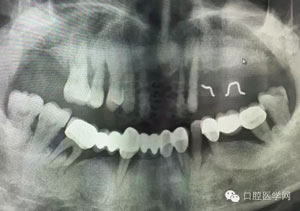

病例1:患者迫切希望保留自己的這一顆牙齒,根尖周陰影比較大,二度松動.而且旁邊有種植修復(fù)體,和患者溝通好后,治療好后觀察一個月后冠修復(fù),因為有種植的后期修復(fù),所以有了機會觀察,術(shù)后三個月和術(shù)后四個月,根尖恢復(fù)的還算不錯,希望能夠繼續(xù)觀察下去.這樣子的病例,做的時候我們一定要非常的小心,和患者要有充分的溝通以及不同科室的溝通然后決定怎么樣做比較好,假如就是出現(xiàn)了問題,到時候我們也比較好處理些,免得我們自己到時候不好收場。